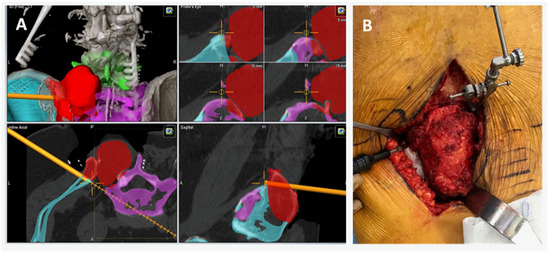

2.1. CAD Development

2.2. Intraoperative CAD Utilization